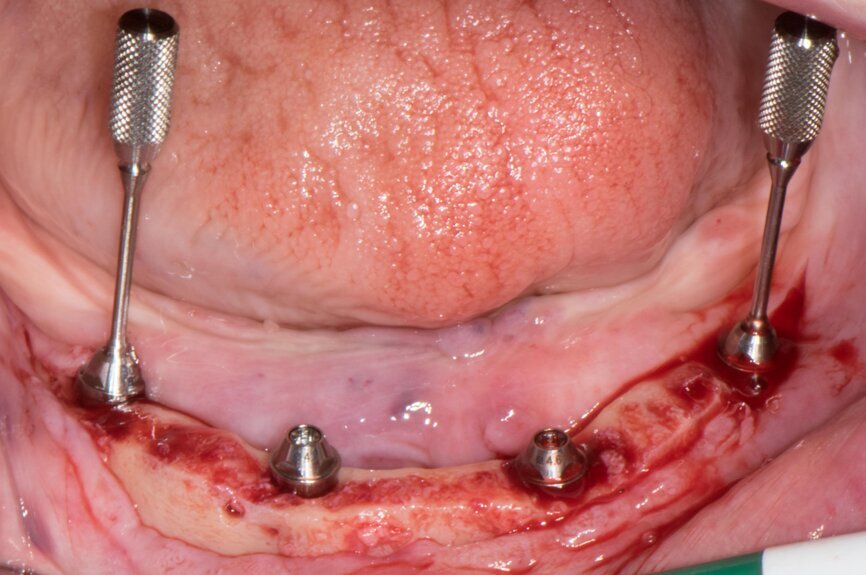

On the day of surgery, two impressions were taken: first with the guide for the pins for stable drilling (Fig. 9), then with the existing prosthesis (Fig. 10) for its correct conversion into an immediate restoration. The first mucosa-supported guide was used for drilling the sites for template fixation pins (Fig. 11). Next, the guide was removed, the flap was raised and the second guide was fixed with the pins at the corresponding sites (Fig. 12).

Implant beds were prepared (Figs. 13 & 14) and Straumann BLT implants placed with a torque setting of more than 35 Ncm, following the protocol to allow correct subsequent screw retained abutment placement (Figs. 15 & 16). Bone around the implants was prepared with bone profilers (Straumann) for the same reason (Fig. 17). The crest was flattened (Figs. 18 & 19), screw-retained abutments were screwed to 35 Ncm (Fig. 20) and covered with healing caps, and the wound was sutured (Fig. 21).